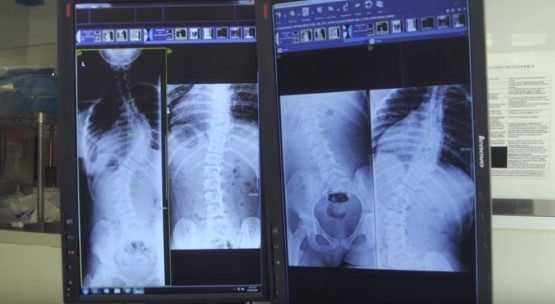

News, Spine

When your spine slips

Spondylolisthesis is a really big word for a condition that causes lower back pain. While it can happen in any part of the back, it commonly occurs when one vertebra in the lower back slips forward over the vertebra below it. A lot of cases of spondylolisthesis stem from arthritis as we age. Jeffrey L….

Read Full Story